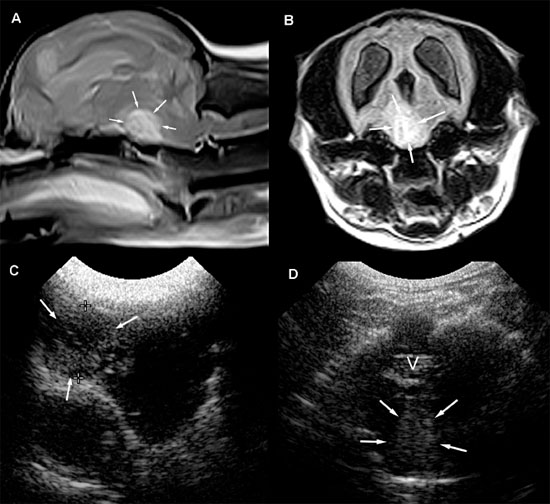

The feline brain can be evaluated by using transverse and longitudinal sonographic planes (Figures 1.5 and 1.6).

The lateral ventricles are slitlike in kittens. In some normal magnetic resonance images of the adult feline brain (Hudson et al. 1995), the lateral ventricles cannot be discerned. Using ultrasound, measurement of lateral ventricles is also more problematic in cats than in dogs because landmarks such as the thalamocaudate groove and the interthalamic adhesion are less recognizable (Jäderlund et al. 2003). In the study by Jäderlund and colleagues, the most reliable and repeatable measurements were obtained by measuring the central portion of the lateral ventricle in parasagittal views angled 5°–10° from the midline. In these images, the dorsal and ventral walls of each lateral ventricle were parallel to each other, but the walls on each side were perpendicular to the ultrasound beam (Figure 1.6). The caudal portion of each lateral ventricle was larger than the more rostral portions, which provided clear visualization in parasagittal scans. Curving of the occipital horn made accurate measurement difficult, however. Difficulty was also experienced when measuring the lateral ventricles in transverse images. Measurement was recommended at the junction of the sella turcica and the cranial fossa to provide a landmark for greater repeatability, but the ventricular walls were at a slightly oblique angle to the beam in transverse images at this level.

Figure 1.5. Transverse sonograms of the brain of a normal 1-week-old kitten. The ventricles in a kitten are slitlike and much smaller than those of a puppy. A: Rostral sonogram showing the caudate nuclei and lateral ventricles (arrows). B: Sonogram with the ultrasound beam perpendicular to the brain. C: Sonogram at the level of the third ventricle. D: Sonogram at the level of the mesencephalon. E: Sonogram with the probe angled caudally to image the cerebellum. The vermis appears as a series of stacked linear echoes. 3, third ventricle; CC, corpus callosum; CG, cingulate gyrus; CN, caudate nucleus (plus the choroid plexus in the lateral ventricle); F, fornix; LF, longitudinal fissure; LV, lateral ventricle; M, mesencephalon; P, pyriform lobe; SS, splenial sulcus; and V, vermis.

Figure 1.6. Sagittal to parasagittal sonograms of the brain of a normal 1-week-old kitten. A: Midline sagittal sonogram. B: Parasagittal sonogram with the beam angled lateral to the midline. CS, callosal sulcus; F, fornix; H, hippocampus; IA, interthalamic adhesion; LV, lateral ventricle; SS, splenial sulcus; and T, thalamus. The arrow in the magnetic resonance image insert shows sagittal and parasagittal planes corresponding to the sonograms.